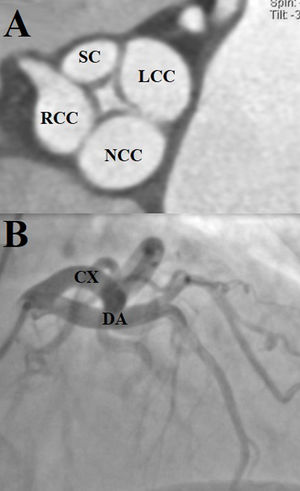

Dilated aortic complex with aortic root measuring 31mm, sinotubular junction 28mm, ascending aorta 35mm, complemented with contrast-enhanced tomography to assess the aorta, which provided clearer images of the aortic valve (Fig. 4A). Coronary angiography identified an independent origin of the left anterior descending artery and the circumflex artery. No atherosclerotic lesions were identified (Fig. 4B).

(A) Contrast tomography. Quadricuspid aortic valve. The supernumerary cusp (SC) is observed between the left and right coronary cusps (Nakamura type I). (LCC: left coronary cusps; RCC: right coronary cusps; NCC: non-coronary cusps). (B) Right anterior oblique projection with skull angulation, showing independent origin of the left anterior descending and circumflex arteries (DA: anterior descending artery; CA: circumflex artery).